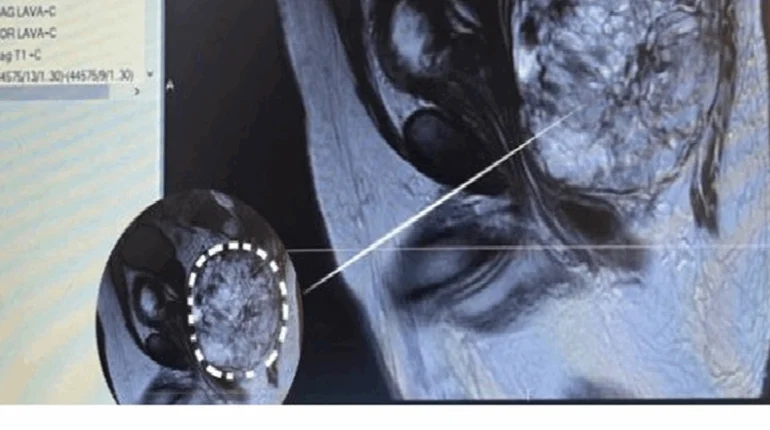

إنجازٌ طبي جديد في لبنان.. إستئصال ورم نادر وهؤلاء “أبطال العملية”!

أعلن مستشفى خلف الحبتور – حرار عكار في بيان، عن “إنجاز طبي جديد اضافته إلى سجله، حيث تم استئصال ورم نادر وضخم من اسفل العمود الفقري مع انتشار الورم نحو الأوعية والأعضاء الحيوية في اسفل البطن”. وأشار الى أن “العملية تمت بنجاح تام مع استئصال الورم بشكل كامل، وكانت زنته حوالي 1600 غ، وقد أجراها […]